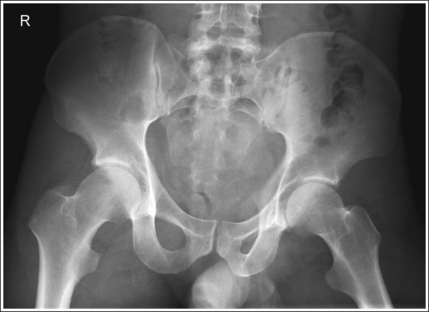

The pelvis demonstrates an AP projection. The ischial spines are aligned with the pelvic brim, the sacrum and coccyx are aligned with the symphysis pubis, and the ilia and obturator foramina are open and uniform in size and shape.

• An AP projection of the pelvis is accomplished by placing the patient supine on the imaging table, with the legs extended and the arms drawn away from the pelvic area (Figure 7-23). To ensure that the pelvis is not rotated, judge the distance from the ASIS to the imaging table on each side. The distances should be equal.

• Pelvic rotation. A nonrotated AP pelvis projection demonstrates symmetrical ilia and obturator foramina. Rotation is initially detected by evaluating the relationships of the ischial spines with the pelvic brim and of the sacrum and coccyx with the symphysis pubis. The ischial spines should be aligned with the pelvic brim, and the sacrum and coccyx should be in alignment with the symphysis pubis on a nonrotated pelvis. If the pelvis is rotated into a LPO position, the left ilium is wider than the right, the left obturator foramen is narrower than the right, the left ischial spine is demonstrated without pelvic brim superimposition, and the sacrum and coccyx are not aligned with the symphysis pubis but are rotated toward the right hip (see Image 16).

• If the patient was rotated into a right posterior oblique (RPO) position, the opposite is true. The right ilium is wider than the left, the right obturator foramen is narrower than the left, the right ischial spine is demonstrated without pelvic brim superimposition, and the sacrum and coccyx are rotated toward the left hip.

The femoral necks are demonstrated without foreshortening and the greater trochanters are in profile laterally, whereas the lesser trochanters are superimposed by the femoral necks.

• Accurate leg positioning. To demonstrate the femoral necks without foreshortening and the greater trochanters in profile on an AP pelvis projection, the patient's leg should be internally rotated until the feet are angled 15 to 20 degrees from vertical and the femoral epicondyles are positioned parallel with the imaging table (Figure 7-24; see Figure 7-21). Sandbags or tape may be needed to help maintain this internal leg rotation. An AP pelvis projection may not demonstrate the proximal femurs with exactly the same degree of internal rotation. How each proximal femur appears will depend on the degree of internal rotation placed on that leg.

• Positioning for a proximal femoral fracture. Often, when a fracture of a proximal femur is suspected, an AP pelvis projection is ordered instead of an AP hip projection because pelvic fractures are frequently associated with proximal femur fractures. If a patient has a suspected fracture or a fractured proximal femur, the leg should not be internally rotated but should be left as is. Forced internal rotation of a fractured proximal femur may injure the blood supply and nerves that surround the injured area. Because the patient's leg is not internally rotated when a fracture is in question, such an AP pelvis projection demonstrates the affected femoral neck with some degree of foreshortening and the lesser trochanter without femoral shaft superimposition.